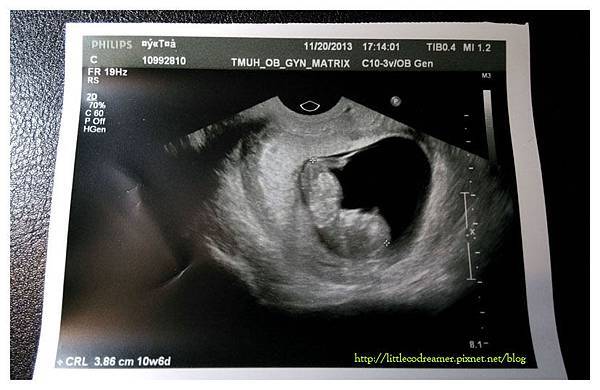

↑目前應有天數為11W~11W3D,超音波算出實際大小為10W6D,(誤差範圍約正負七日內)。看得出來寶寶有點人形了,腿的部分還是芽苞狀。目前身長(頭臀距離)已有3.86CM。

按時服完了三天份屬於B級感冒藥,咳嗽有稍微好轉,但仍未痊癒。一方面也是擔心寶寶受到影響的程度,所以決定回北醫掛婦產科門診。當天是給區慶建醫生看診。自費照完超音波後,得知寶寶健康無恙,鬆了好大一口氣。